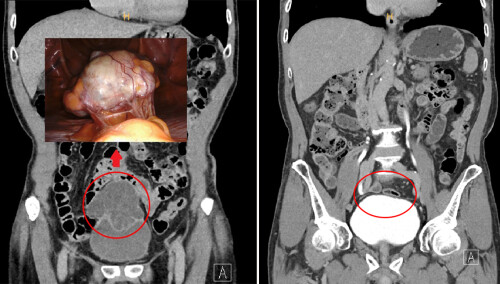

| ▲희귀 거대 요관막암 제거 전 CT 사진(좌측)과 3D 영상 사진(좌측 상단), 제거 후 CT 사진(우측) 비교 (사진=순천향대 부천병원 제공) |

환자는 71세 남성으로 8cm 크기의 큰 암 덩어리가 배꼽 직하부 요막관에 자리 잡아 방광까지 침범한 상태였다. 고령인 데다가 혈관이 매우 발달해 있어 수술 시 극심한 출혈 가능성이 크고, 해부학적인 파악도 쉽지 않아 고난도 수술이 예상됐다.

이에 이상욱 교수는 다빈치 Xi 로봇수술을 택했다. 수술 부위를 3D 영상으로 15배까지 확대해보면서 자유롭게 회전하는 로봇 팔을 이용해 정밀하게 요막관 제거 및 방광 부분 절제술을 시행하여 거대 요막관암을 제거했다.